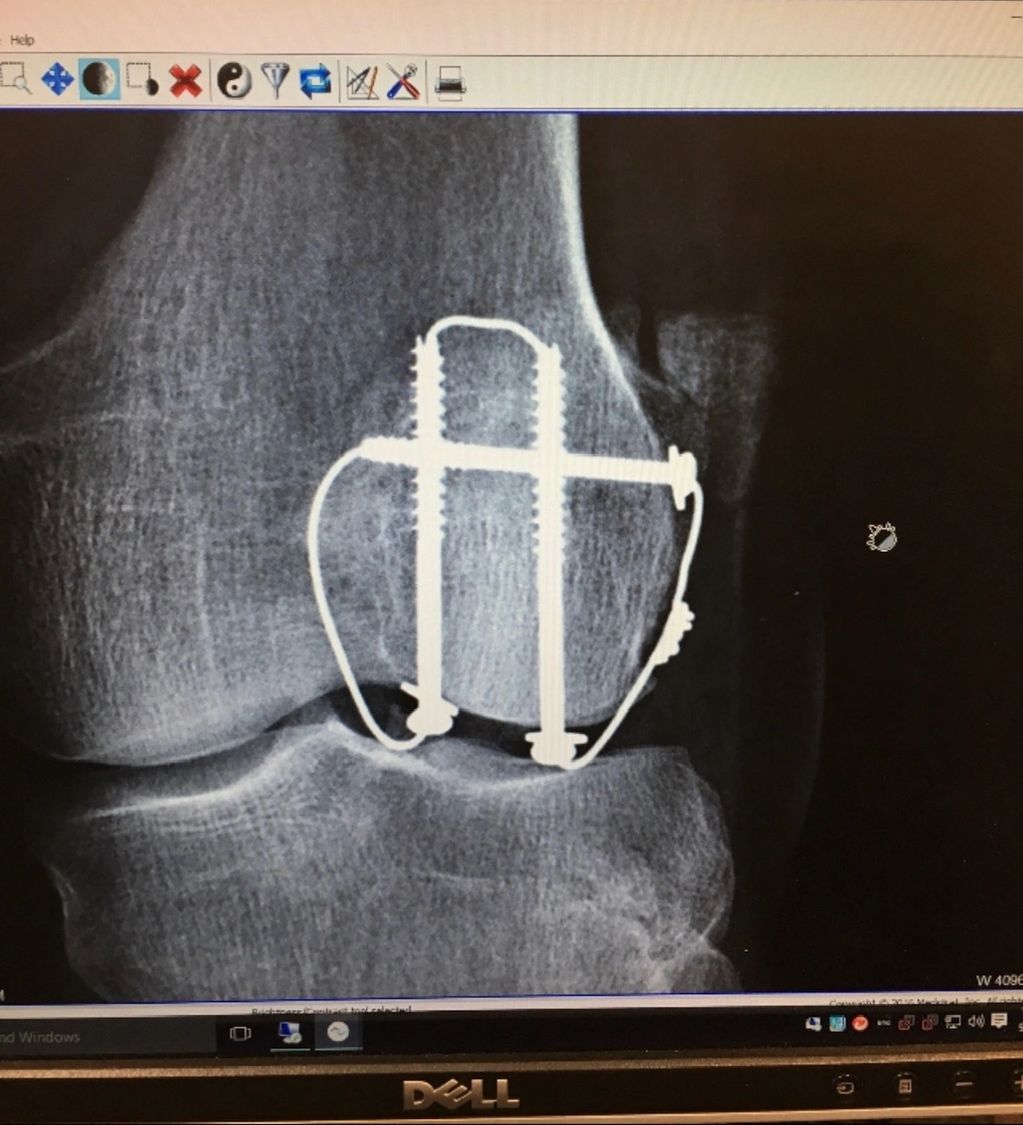

My fractured knee cap with its hardware. To this day it's very hard and painful to walk